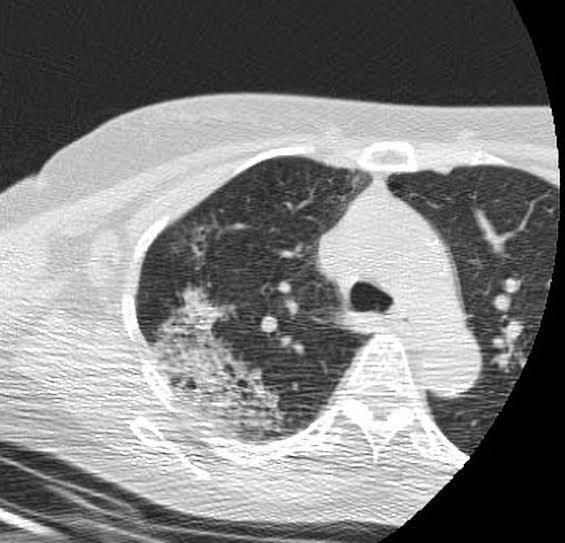

8) Imaging

• CXR: Bilateral diffuse alveolar infiltrates (ARDS pattern)

• CT Chest (Day 2): Diffuse ground-glass opacities with patchy alveolar hemorrhage